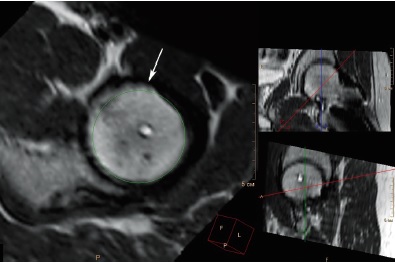

Фиброцисты в наших наблюдениях отчетливо визуализировались в 8 (25,0%) из 32 суставов со смещением эпифиза, величина передневерхнего угла α в каждом из этих 8 суставов превышала 55° (рис. 5).

Рис. 5. МРТ левого тазобедренного сустава пациентки 18 лет 4 мес. через 4 года 5 мес. после операции, аксиальная проекция, режим с жироподавлением. Фиброциста (обозначена стрелкой), локализующаяся у передневерхнего края шейки бедренной кости на краю суставной поверхности, в месте столкновения